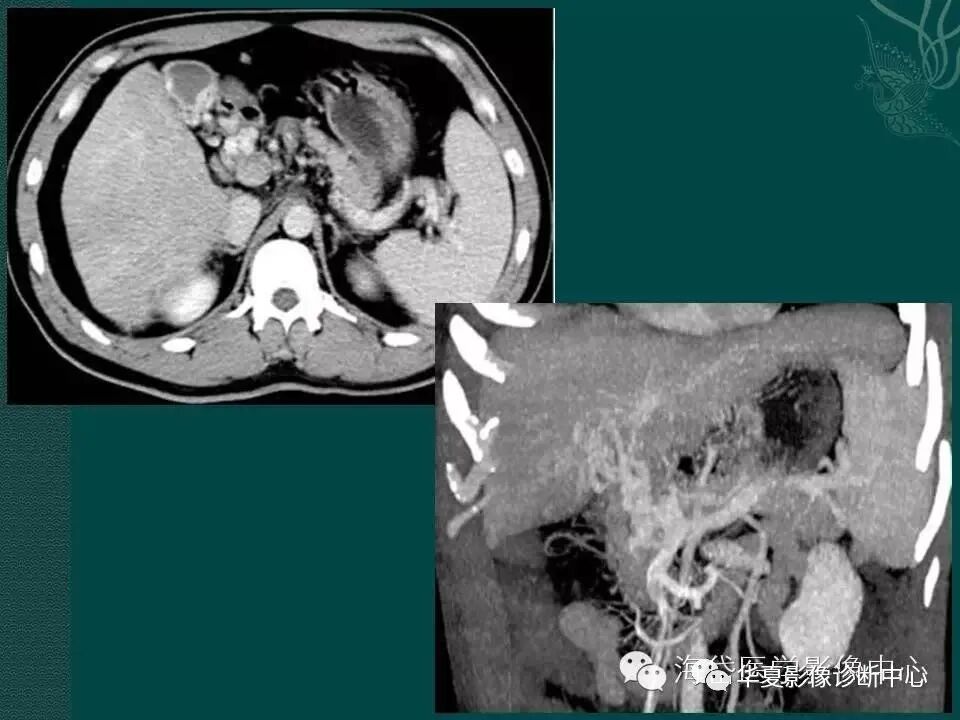

患者,女,30岁,不明原因出现便血,急诊就诊,血色素45g/L,予以输血,否认肝炎、肝硬化。超声提示:巨脾;腹部增强CT提示:上腔静脉血栓考虑,肝门显示不清,巨脾。胃镜提示:胃-十二指肠静脉曲张。

这是一个病史的简单汇报,不管是影像科医生还是临床医生,我们是否想到过CTPV(门静脉海绵样变性)的可能。为了一起学习这个病,借鉴海岱医学影像中心的PPT,共勉。